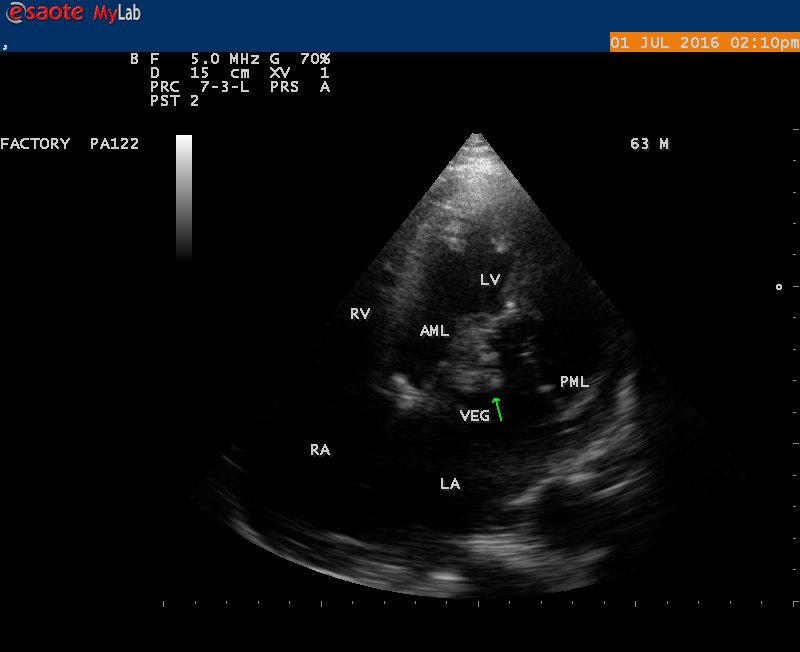

The most common and direct evidence of infective endocarditis is the vegetation and it begins as a microscopic focus of infection and gradually grows into a conspicuous mass. It is typically an irregularly shaped, highly mobile, echogenic mass attached to the free edge of a valve leaflet ( most commonly at the coaptation line) and tends to develop on the ‘upstream’ side of the valve leaflets ( ie, the ventricular side of aortic valve and the atrial side of mitral and tricuspid valves. They may be seesile or pedunculated, but usually has an oscillating or fluttering motion, a typical feature of most vegetations. Vegetation move with the leaflet in a more chaotic (‘oscillating’) manner and it may prolapse through the valve into the LV (left ventricle) as it opens as shown in Figures 3, 4 and 16 and into LA (left atrium) as it closing (Figure 5 and 6) . The mass of vegetation is typically homogeneous with echogenicity similar to that of the myocardium. The infectious process often alter the valvular structure and function. Extensive involvement of the leaflet may result in chordal rupture, leading to severe regurgitation as shown in Figure 21 . Direct and typical signs of RMCT (ruptured mitral chordate tendineae) were chain-flail or whiplash-like changes and had an incidence of 86.7%, causing severe regurgitation and mitral chordal rupture is the leading cause of flail mitral leaflet[30]. A large vegetation may obstruct the valve orifice as shown in Figure 1 and 2 , sometimes termed as “obstructive-type bacterial endocarditis” and producing a functional valve stenosis ( Ping-Pong mitral stenosis [31]) similar to left atrial myxoma as shown in Figure 29.

The shape and size of vegetation are quite variable and mostly it is polypoid [32]. The typical vegetation is a ‘sessile’ or ‘ pedunculating’ valve – attached mass. A ‘sessile’ vegetation had to be completely attached to the valve as shown in Figures 34 and 35 in a 63- year old male, in which a large vegetation is attached to the atrial side of anterior mitral leaflet [33-Figure 13.3-A], producing severe mitral regurgitation as shown in Figure 36 and a mobile vegetation showed a pedunculating part prolapsing into the ventricle as shown in Figure 3 and 4 or atrium as shown in Figure 5 [33-Figure 13.1] in a 10-year old female child. A vegetation was considered as ‘definite’ when shaggy echoes in the M-mode study as shown in Figure 20 . and a corresponding mass without restricted valve motion in the two-dimensional echocardiogram were found as shown in Figure 16 and 30 [33-Figure 13.7]. The vegetation vary in size, often being just a few mm and sometimes reaching to 2-3 cm. A vegetation must be atleast 3 to 6 mm in size to be reliably seen. The mean size of vegetation was 0.6 mm (range 3 to 28) and vegetation > 10 mm in diameter was defined as ‘large’ and those ≤ 10 mm in diameter was defined as ‘small’ and ≥ 15 mm is ‘very large’. Vegetations resulting from fungal infections (candida, aspergillus) are usually much bigger than bacterial vegetations and can be so big to be mistaken for a cardiac tumor. The large vegetations are at increased risk for embolic complications [34], especially on the anterior leaflet of the mitral valve with mobility [35]. A vegetation size of 3.2 x 4.4 cm is called as ‘giant vegetation’ on the mitral valve with a fibrillary appearance of the mass [36- Figure 3] as shown in Figure 1 is an important predictor of embolic phenomena in patients with infective endocarditis causing severe mitral regurgitation as ‘Duck’ shaped jets (Figures 24 and 25 ), disorganized (Figure 21) and sometimes the regurigitant jet splits into two components as one into LA and the second one into LV simultaneously as a bileaflet jets (Figure 10 ) similar to bileaflet structure of AML with vegetation masses (Figure 9 ) . The size of the largest vegetation reported on the mitral valve in the literature in patients with bacterial endocarditis is 7x4 cm[37]. In a study of Nunes, et al[38], vegetation size >13 mm was the only independent predictor of mortality, but some studies [39],[40] did not had an increased embolic risk in patients with vegetation focused only on its presence and size and not on their location. Embolic complications may occur in infective endocarditis(20.6%)and were not more prevalent in the groups with large vegetations [41]. However, Wong, et al [42] found an increased need for surgery in patients with a large vegetation (>10 mm).

The size and shape of vegetation vary due to curling of vegetation. The size of vegetation in this child is 35.6 x 9.3 mm as in Figure 17 , 20 x 23.7 mm as in Figure 1 , 32.9 x 13.9 mm as in Figure 2 .

The shape of vegetation varies in this child as ‘popcorn’ like (Figures 1,3 and 4 ), rod-shaped (Figure ), basket shaped (Figure 7 )[33-Figure 13.3], ‘baby in hand’ appearance (Figure 18), ‘cucumber shaped (Figure 2 ) and a ‘bunch of plantain’appearance (Figure 33 ), ring shaped (Figure 19 }, bileaflet structure (Figure 9 )with bileaflet MR jet as shown in Figure 10 . and kissing forms (Figure 13 - parasternal long axis view, Figure 14 - apical four chamber view and Figure 15 - short axis view)